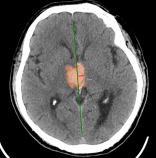

Chẩn đoán hình ảnh mô mềm tiên tiến cho vùng bụng.

Tăng cường độ tương phản I-ốt.

Hỗ trợ đánh giá an toàn cho bệnh nhân.

Đảm bảo hình ảnh chất lượng cao.